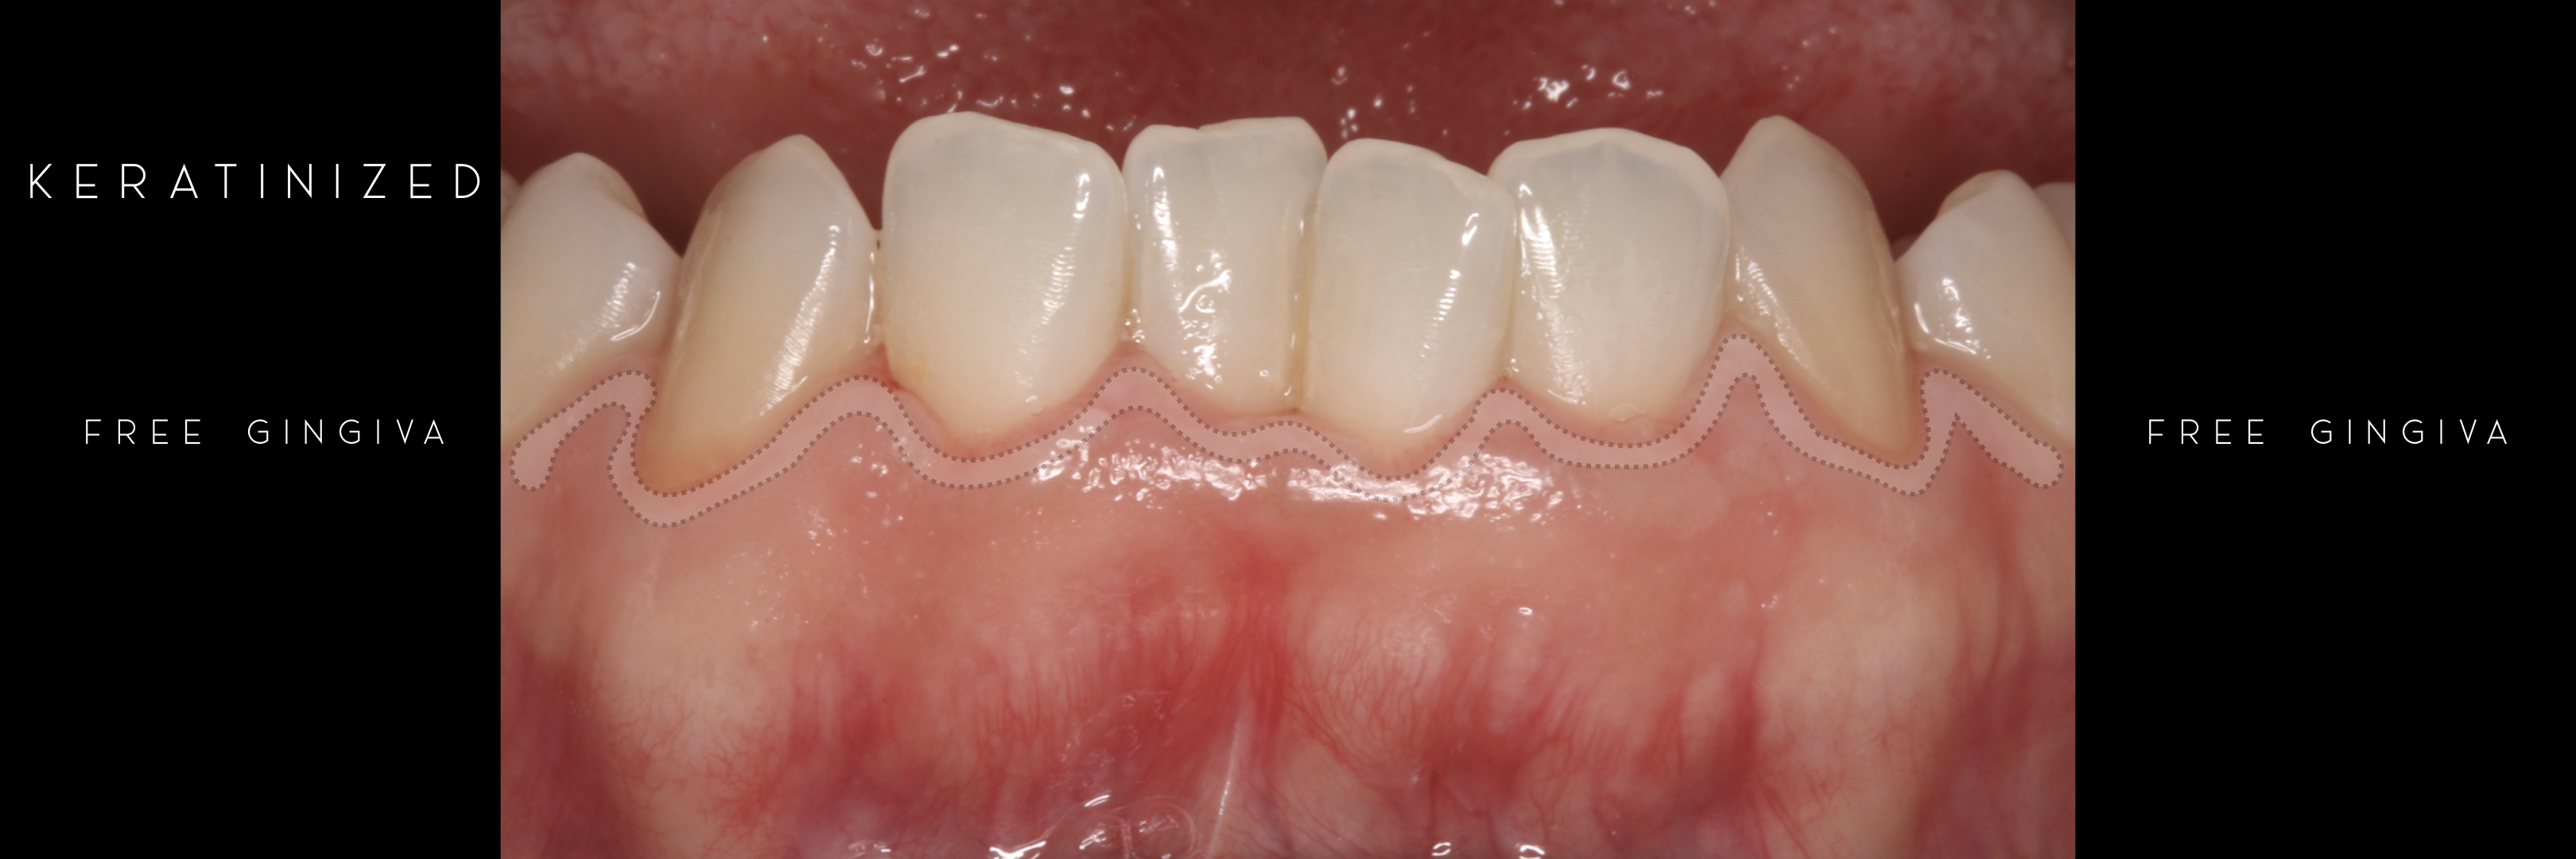

KERATINIZED gingiva includes

the free gingiva

(marginal gingiva & papillae)

Generally we tend to forget about these 2 parameters, free and the attached gingiva are both essential parts of the keratinized gingiva.

However free marginal gingiva is different in characteristics on its outer and inner surfaces: outer surface is keratinized;

inner surface is

non-keratinized, constituting part of the gingival sulcus.